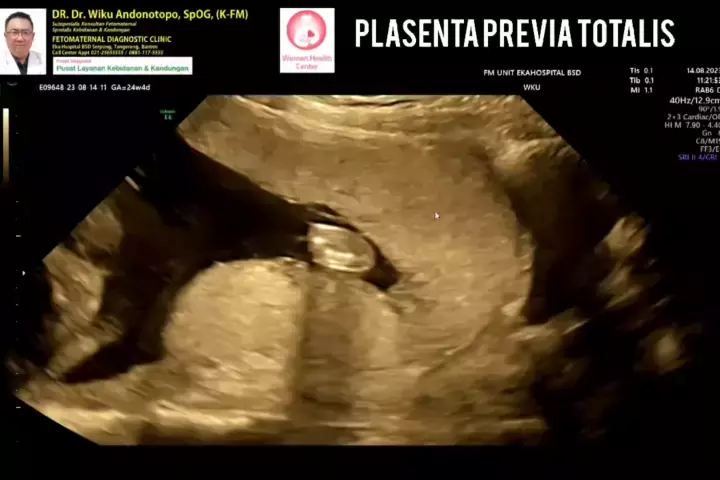

Plasenta Previa Totalis... #drwikuandonotopo #konsultanfetomaternalpontianak #fetomaternalpontianak #konsultanfetomaternalsemarang #usgfetomaternaltangerang #fetomaternalsemarang #usgfetomaternalbsd #ekahospitalbsd #fetomaternal #spog #polikandunganekahospitalbsd # #plasentaprevia #plasentapreviatotalis #placentaprevia